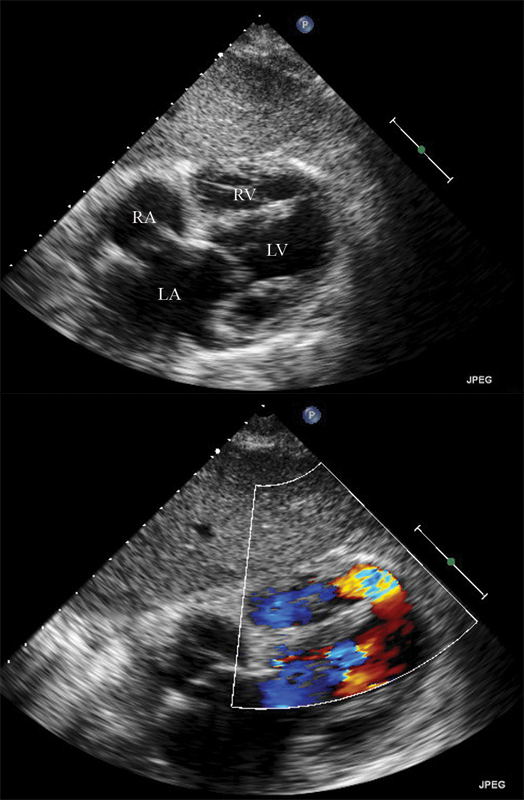

فحوصات تشخيصية لبعض امراض القلب والشرايين التاجية